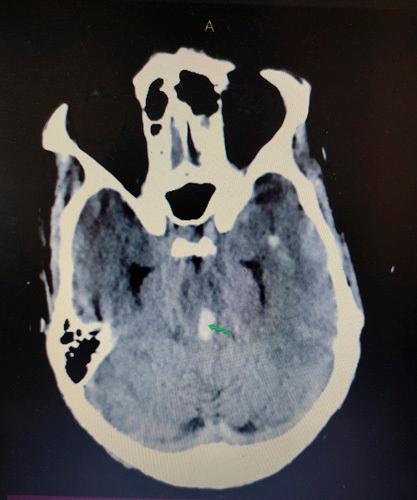

The patient was managed conservatively in the Neurosurgical Intensive care unit. Supportive management was provided. The patient's motor response was improving and a repeat CT scan showed a resolving haematoma. However, due to poor economic conditions, the patient party left against medical advice.

患者在神经外科重症监护病房接受保守治疗。给予支持性治疗。患者的运动反应有所改善,复查CT扫描显示血肿正在吸收。然而,由于经济条件差,患者家属违背医嘱离院。